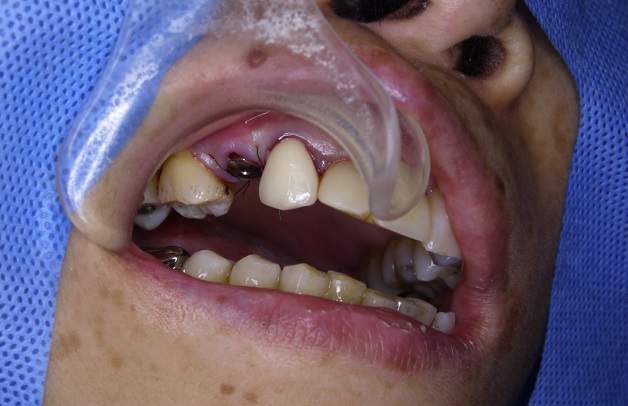

很多人說,拔牙了有洞就直接放植體進去就好,

但儘管只是簡單的手術,還是有存在著相當程度的風險,

所以我們皆會使用手術導板

手術的過程中搭配手術導板

既能減小傷口

又能加快手術時間

術後隔天,患者說沒什麼感覺,連止痛藥都只吃了一顆